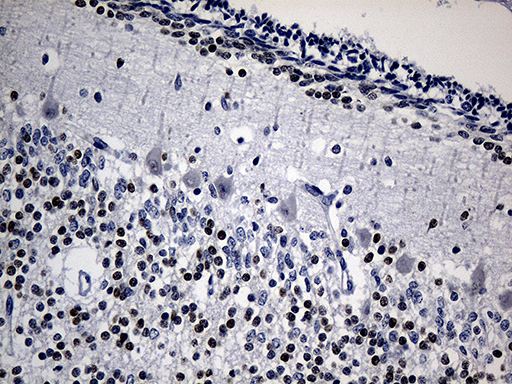

- Experimental details

- Immunohistochemical staining of paraffin-embedded Human embryonic cerebellum within the normal limits using anti-PHF20L1 mouse monoclonal antibody. (Heat-induced epitope retrieval by 1mM EDTA in 10mM Tris buffer (pH8.5) at 120 oC for 3 min, TA809761)(1:150)

- Validation comment

- IHC